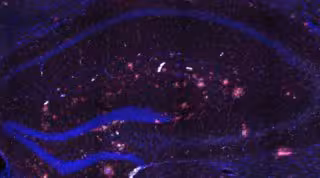

Las células de la microglía son células inmunitarias que se encuentran en el cerebro y la médula espinal, cuya función principal es actuar como la primera línea de defensa del sistema inmunológico en el cerebro. "Actualmente, la microglía ha cobrado un papel fundamental en la investigación del Alzheimer porque estas células actúan para contener el daño de la patología, pero su activación prolongada puede agravar la degeneración cognitiva. Esta dualidad hace que el estudio que planteamos sea clave para entender mejor la evolución de la enfermedad", explica De Santis.

El laboratorio Biomarcadores de Imaging Traslacional que lidera la investigadora en el IN ha desarrollado una nueva técnica de imagen cerebral no invasiva, basada en imagen por resonancia magnética ponderada en la difusión de agua, que permite monitorizar la microglía. El objetivo del proyecto es aplicar esta tecnología en un modelo animal de la enfermedad de Alzheimer y, posteriormente, adaptarla a pacientes humanos.